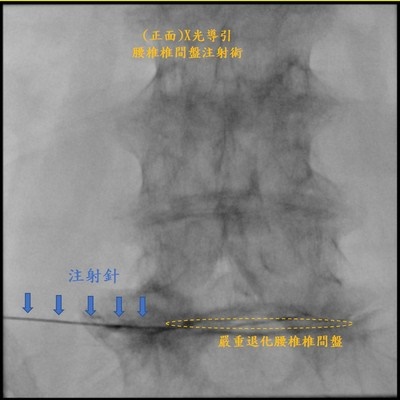

王柏凱主任說,當時詹女士的第五腰椎跟薦椎間中間的椎間盤嚴重退化,因神經孔過小壓迫到神經,導致左邊的坐骨神經痛,當時做了硬脊膜外注射、增生療法等治療,疼痛明顯改善,但是效果只能維持約三個月;詹女士因為有膝蓋的骨內注射療法大大改善疼痛的經驗,與病人討論後,在今年七月的腰椎治療,也加入了骨內注射治療,如今詹女士已五個月沒感受到腰痛了。

圖說:花蓮慈濟醫院麻醉部疼痛科王柏凱主任為詹女士做骨內注射治療